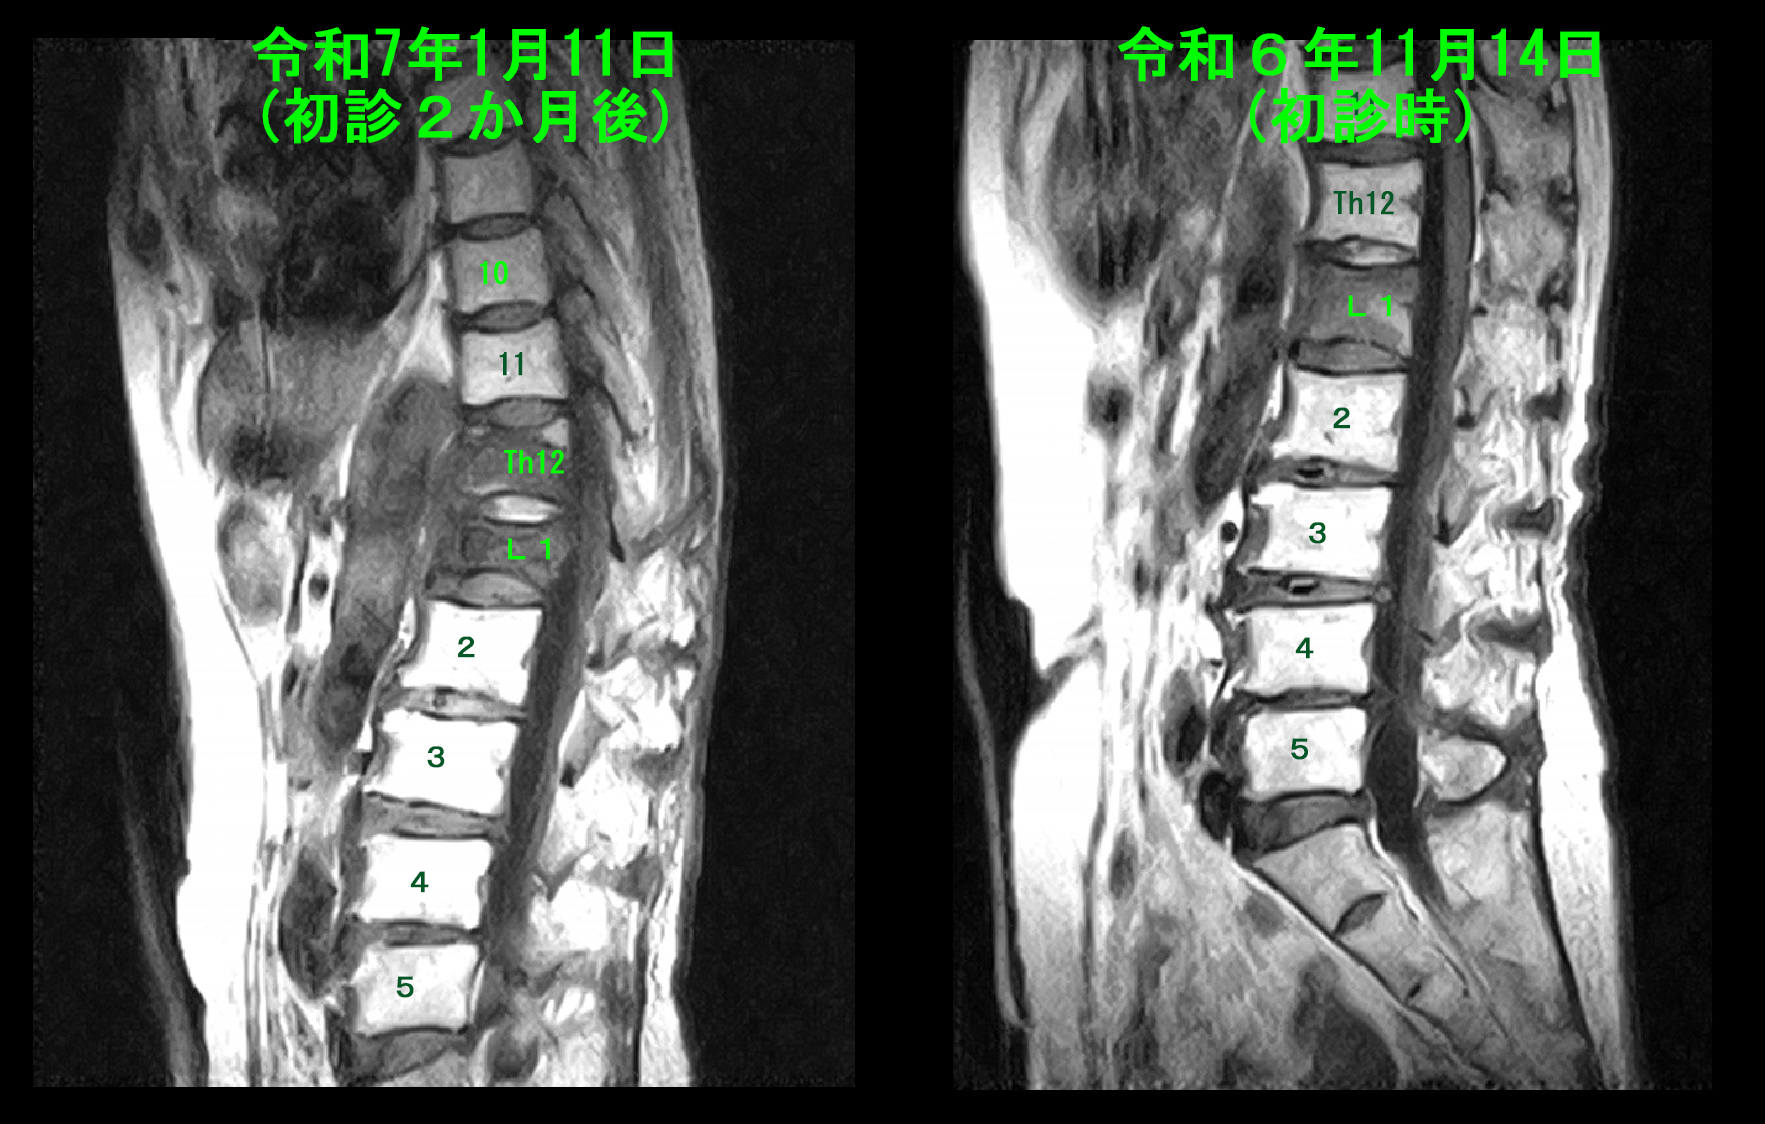

1月11日(初診から2か月後)には患者さんは腰痛は大分楽になったと述べていましたが、レントゲン像ではL1椎体の上の第12胸椎の扁平化が確認され(赤矢印)、MRI検査を行いました。

MRI検査(T1条件)では、第12胸椎が低輝度化しており、圧迫骨折を発症したことが確認されました。

圧迫骨折の治療が適切に行われないと、圧迫骨折のドミノ現象と言われる隣接椎体に圧迫骨折が次々と波及することが見られることが時々あります。圧迫骨折のドミノ化現象も、圧迫骨折が診断された患者さんに渡すパンフレットには記載していますが、専門家のアドバイスを尊重しない姿勢で読んでも、パンフレットはパンフレットで私のことではないと自分の思い込みが優先しているのだと思います。

2月9日(初診から3か月)遷延化した腰痛のために自分で動けない時期が長くなったために、当院で起立歩行のリハビリテーションを開始し、4月5日までには自分で車いすへの移乗が可能となりました。レントゲン像では初診時に比して背骨の円背がぐっと進行していることが分かります。4月5日の時点で主人が転倒し圧迫骨折を受傷されてしまい、奥さん1人では生活できないために息子さんの介護を受けながら施設への短期入所を繰り返す経過となり、当院でのリハビリは中断しています。半年後に受診されたときにはほとんど歩けない状態となっていました。